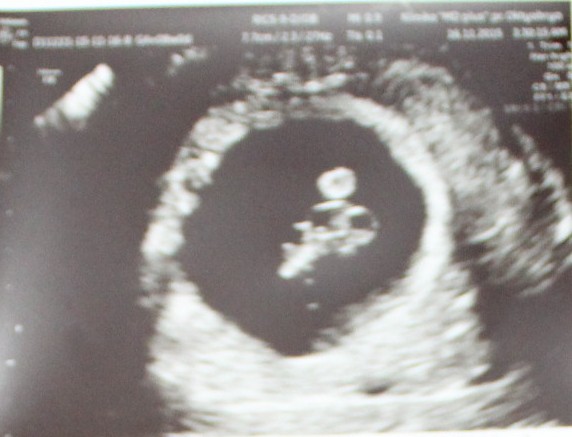

Итак УЗИ, увидела на экране : маленькое чудо. Ура мы растем, нам уже 7 недель и 6 дней, 15 мм, сердечко бьется 162 ударов в минуту, и послушала и увидела!!!- это просто волшебно, всю консультацию сидела с широкой улыбкой до ушей. СМОТРЕЛА БЫ ВЕЧНО!!! Даже мини-пуповинку показали. Вообщем у нас все хорошо.

Про центр скажу отдельно, специалист у меня была прекрасной: все объяснила, показала, сделала как на животе, так и трансвагинально, одни только положительные эмоции. А вот и мы:![]()